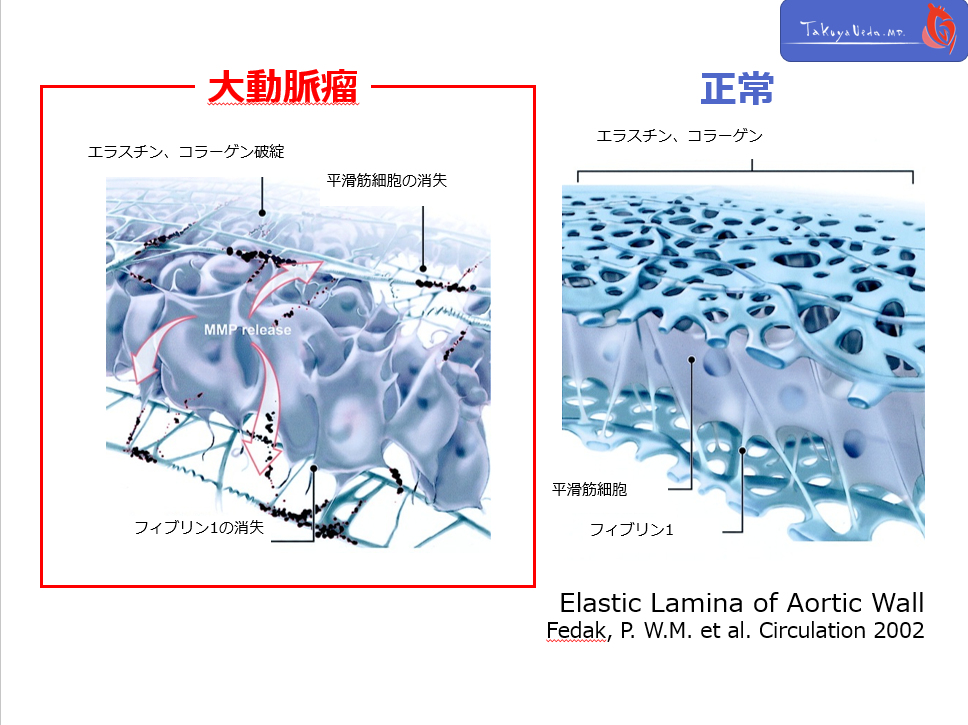

各病態の疾患概念を考える際に、大動脈の壁構造を理解することは非常に重要です。

大動脈壁は、Intima, Media, Adventitiaの3層構造よりなり、各層間をelastic laminaが区分しています。

CT上、これらの層構造自体を観察をすることはできませんが、どの構造に異常が存在するのかということを意識する事で、pathophysiology理解の助けとなります。

各病態の疾患概念を考える際に、大動脈の壁構造を理解することは非常に重要です。

大動脈壁は、Intima, Media, Adventitiaの3層構造よりなり、各層間をelastic laminaが区分しています。

CT上、これらの層構造自体を観察をすることはできませんが、どの構造に異常が存在するのかということを意識する事で、pathophysiology理解の助けとなります。

各病態の疾患概念を考える際に、大動脈の壁構造を理解することは非常に重要です。

大動脈壁は、Intima, Media, Adventitiaの3層構造よりなり、各層間をelastic laminaが区分しています。

CT上、これらの層構造自体を観察をすることはできませんが、どの構造に異常が存在するのかということを意識する事で、pathophysiology理解の助けとなります。